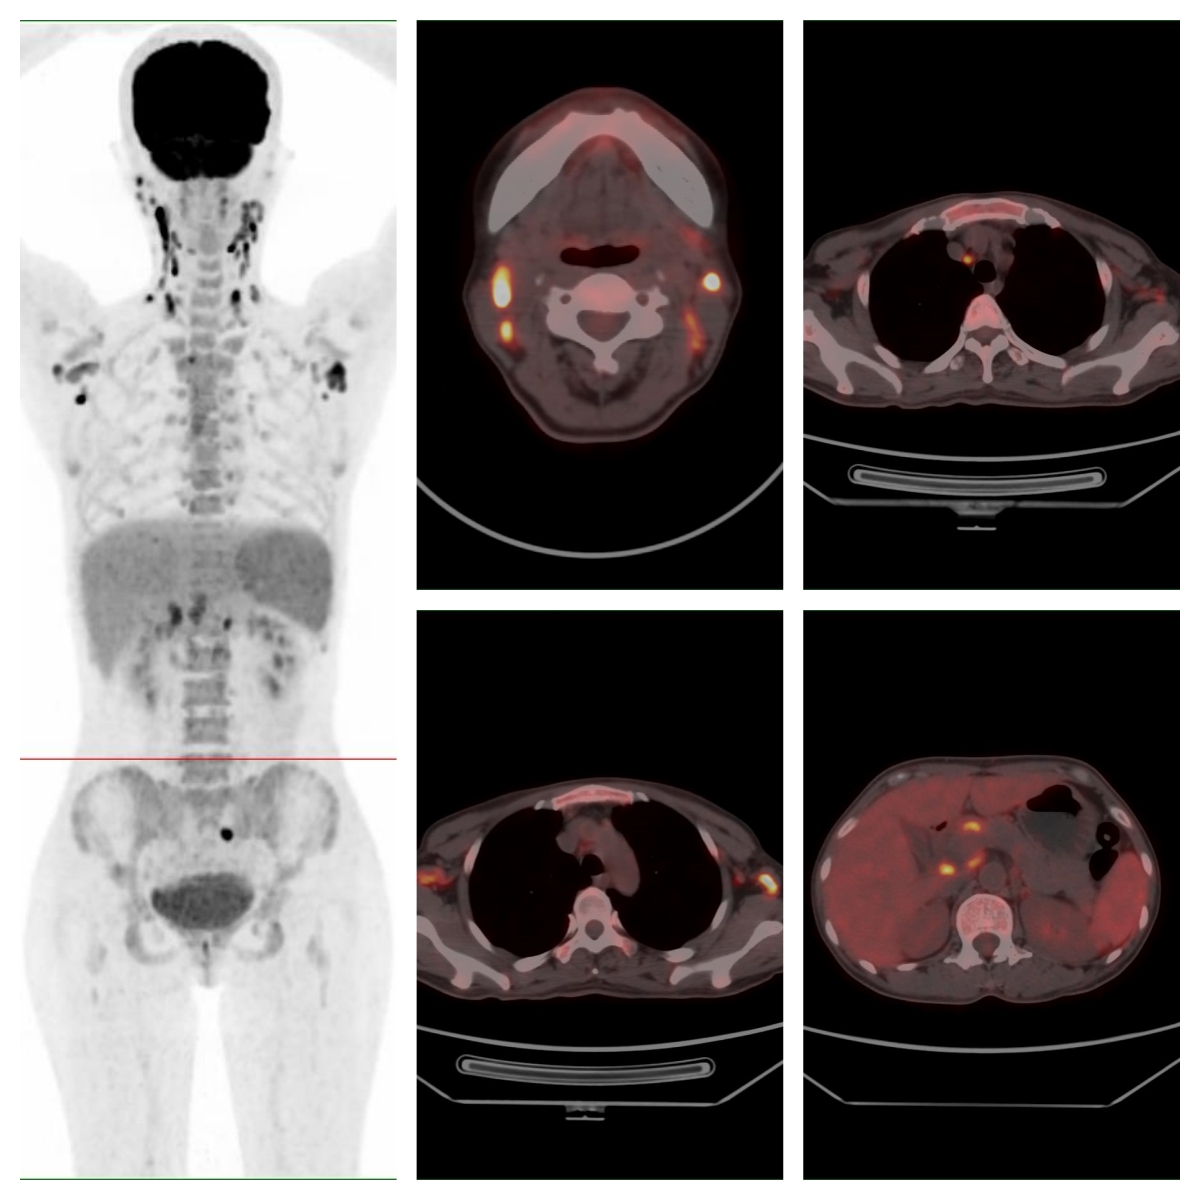

為明確病情,完善PET/CT檢查

PET/CT示全身多處淋巴結(jié)、多處骨骼及脾臟代謝異常,考慮系統(tǒng)性疾病(圖示);顯像劑攝取最高者位于右側(cè)頸部Ⅱ區(qū),SUVmax約19.6。

圖 全身多處淋巴結(jié)、骨骼及脾臟代謝異常。

經(jīng)多學(xué)科會診,對右側(cè)頸部代謝最高的淋巴結(jié)進(jìn)行了完整切除活檢,病理示外周T細(xì)胞淋巴瘤-非特指型。